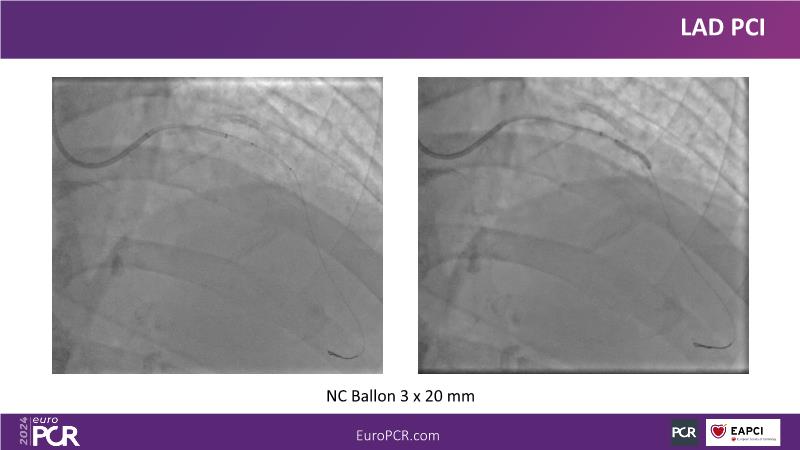

Explore this session to uncover the common association between calcium and acute coronary syndrome, and how intravascular lithotripsy (IVL) offers a safe solution for calcified lesions, with comparable procedural success rates. However, note that ACS cases involving calcium may lead to higher major adverse cardiac events (MACE). Special attention is warranted for women due to their propensity for adverse outcomes. Discover how the C2 + IVL catheter enhances procedural flexibility, yet high intracoronary imaging rates did not yield differences in MACE. Additionally, learn about the potential role of IVL in treating in-stent restenosis (ISR).

- To share clinical experience to uncover practical tips and techniques for intravascular lithotripsy in complex calcified lesions